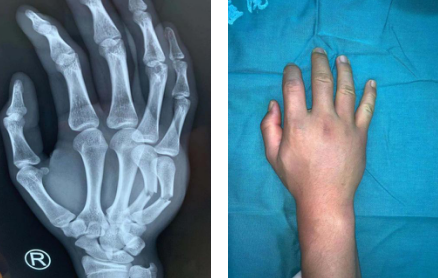

术前

6月15日下午,一名初三的学子强强(化名)放学回家后,正准备把自行车推到小区的地下车库,由于未注意到脚下的缓冲带,一下子摔了一跤,当时他立刻感觉到右手疼痛、肿胀。回到家中,他给妈妈打电话,说出事了。妈妈一听,心里非常担心,赶回家看到儿子的右手背肿得很高,才了解到儿子摔伤了,于是急忙带他前往必威官方首页官网betway就诊。

我院急诊科通知手外四病区的值班医疗小组接诊,建议患者办理住院手续尽快手术。强强的妈妈说,6月18日强强要参加中考,不能耽误,她必须把这个特殊的情况向医生说明。接诊的医生介绍,强强右手第4、5掌骨骨折,其他部位未受伤。如果手术,术后两三天内不能完全消肿,可能会影响中考;如果不在24小时内手术,可以选择5-7天左右消肿后再手术。延缓手术肯定会影响恢复,但是从强强目前的情况考虑,先中考,再手术是比较好的选择,男子汉大丈夫,忍一忍疼痛应该是没问题的。强强当即决定出院,好好准备中考。出院前,医生帮他用夹板外固定骨折。